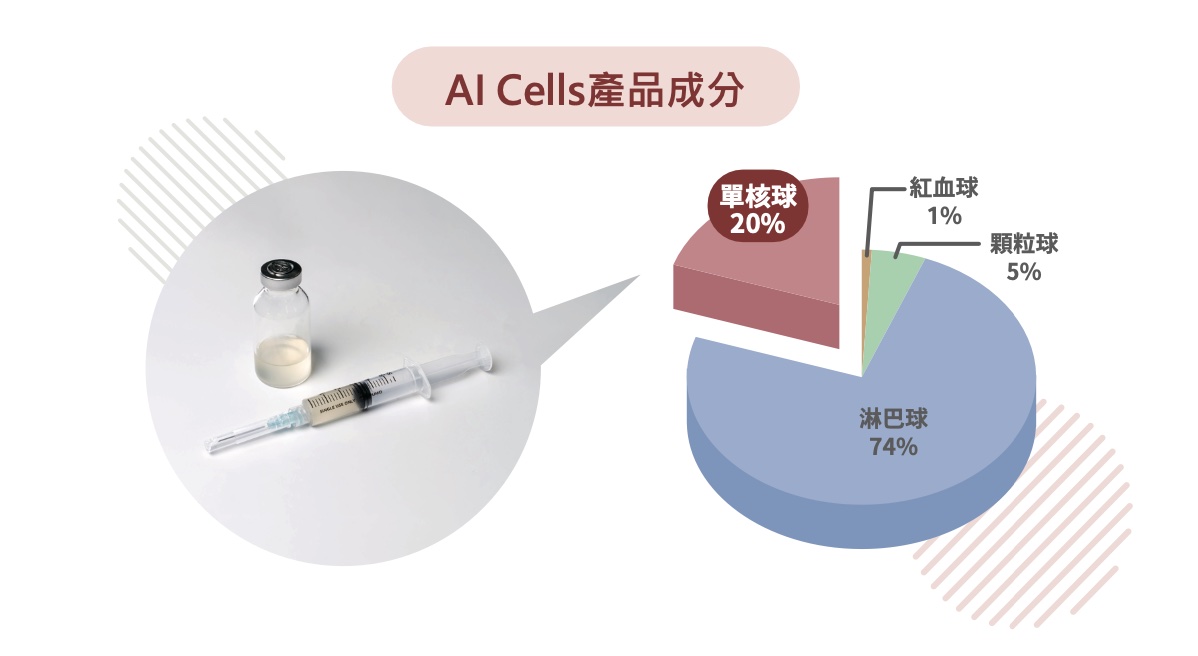

PCP / AI Cells 純化流程與產品成分

PCP 周邊血液單核細胞純化技術的主要流程包含:抽血 50–80 c.c.、單核球富集、去除嗜中性球、細胞定量與品質管制,以及由專科醫師施打。產品成分圖中顯示,純化後的 AI Cells 主要組成以淋巴球與單核球為主,其中單核球約占 20%,可作為支持療程抗發炎與修復概念的重要基礎。